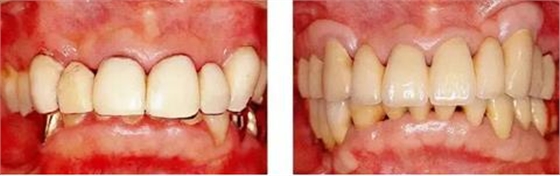

病例1 除去不良修復(fù)體后,進(jìn)行牙周外科,制造出容易進(jìn)行菌斑控制的環(huán)境的病例。

圖16-1(左) 主訴為前牙處的美學(xué)問題的55歲男性患者的初診時(shí)的口腔正面照。上頜前牙處的修復(fù)體有大小不合適、形態(tài)等為題,處于不容易被清潔的狀態(tài)。另外,上頜前牙處的牙齦非常薄,露出修復(fù)體邊緣的狀態(tài)。這種狀態(tài)很有可能會讓牙齦附著進(jìn)一步喪失。

圖16-2(右) 戴上最終修復(fù)體8年后的狀態(tài)。進(jìn)行了去除牙周袋以及獲得附著牙齦為目的的牙周外科,制作了便于清潔的修復(fù)體,這樣一來就可以維持安定的口腔內(nèi)狀態(tài)。